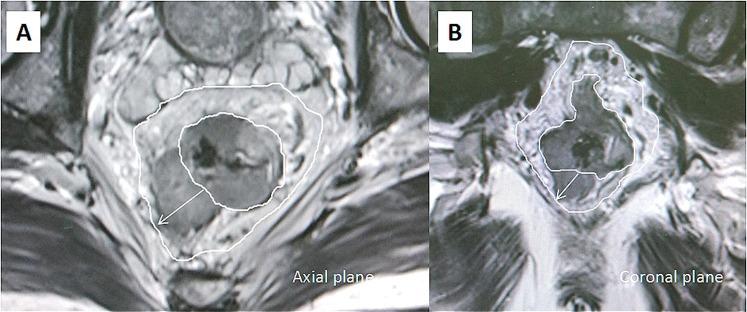

The purpose of this study was to evaluate the prognostic significance of the magnetic resonance imaging-detected extramural venous invasion (MR-EMVI), the depth of mesorectal extension (MR-DME), and lymph node status (MR-LN) in clinical T3 mid-low rectal cancer. One hundred and forty-six patients with clinical T3 mid-low rectal cancer underwent curative surgery were identified. Pretreatment high-resolution MRI was independently reviewed by two experienced radiologists to evaluate MR-EMVI score (0-4), MR-DME (≤4 mm or >4 mm), and MR-LN (positive or negative). The Cox-multivariate regression analysis revealed that the MR-EMVI was the only independent prognostic factor that correlated with overall 3-year disease-free survival (DFS) (p = 0.01). The survival analysis showed that patients with positive MR-EMVI, MR-DME > 4 mm, and positive MR-LN had a poorer prognosis in the overall 3-year DFS (HR 3.557, 95% CI 2.028 to 13.32, p < 0.01; HR 3.744, 95% CI:1.165 to 5.992, p = 0.002; HR 2.946, 95% CI: 1.386 to 6.699, p < 0.01). By combining MR-EMVI with MR-DME or MR-LN, the prognostic significance was more remarkable. Our study suggested that the MR-EMVI, MR-DME, and MR-LN were the important prognostic factors for patients with clinical T3 mid-low rectal cancer and the MR-EMVI was an independent prognostic factor.

本研究旨在评估磁共振成像检测到的外膜静脉侵犯(MR-EMVI)、直肠系膜延伸深度(MR-DME)和淋巴结状态(MR-LN)在临床 T3 中低位直肠癌中的预后意义。我们确定了 146 例接受根治性手术的临床 T3 中低位直肠癌患者。两名经验丰富的放射科医生对术前高分辨率 MRI 进行独立评估,以评估 MR-EMVI 评分(0-4 分)、MR-DME(≤4mm 或>4mm)和 MR-LN(阳性或阴性)。Cox 多因素回归分析显示,MR-EMVI 是唯一与总 3 年无病生存率(DFS)相关的独立预后因素(p=0.01)。生存分析显示,MR-EMVI 阳性、MR-DME>4mm 和 MR-LN 阳性的患者总 3 年 DFS 预后较差(HR 3.557,95%CI 2.028-13.32,p<0.01;HR 3.744,95%CI:1.165-5.992,p=0.002;HR 2.946,95%CI:1.386-6.699,p<0.01)。通过将 MR-EMVI 与 MR-DME 或 MR-LN 相结合,预后意义更加显著。我们的研究表明,MR-EMVI、MR-DME 和 MR-LN 是临床 T3 中低位直肠癌患者的重要预后因素,MR-EMVI 是独立的预后因素。